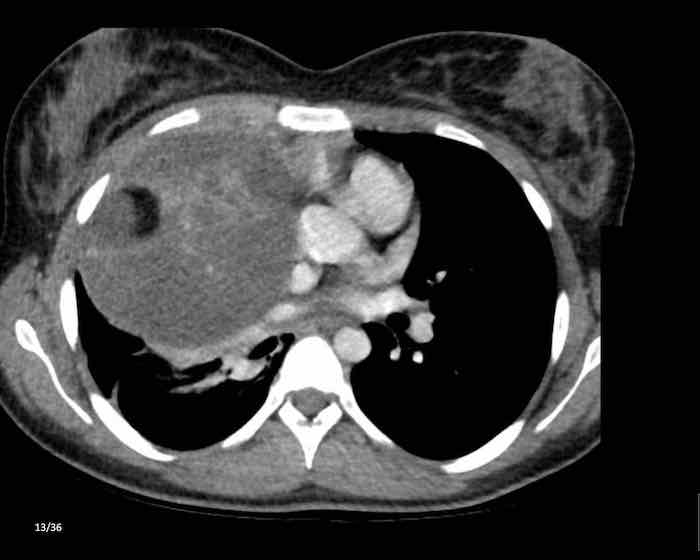

Các hình ảnh này của một phụ nữ 65 tuổi có tiền sử mắc bệnh Graves, một rối loạn tự miễn liên quan đến tình trạng cường chức năng tuyến giáp.

CT được thực hiện vì lý do ho ra máu.

Hình ảnh

Có một tuyến ức to lớn, cồng kềnh chứa mô mỡ đại thể.

Đây là hình ảnh điển hình của tăng sản tuyến ức.

Tăng sản tuyến ức trong bệnh Graves có liên quan đến tình trạng dư thừa hormone tuyến giáp và kháng thể kháng thụ thể thyrotropin.

Tình trạng này thường cải thiện sau khi điều trị thành công bệnh Graves.